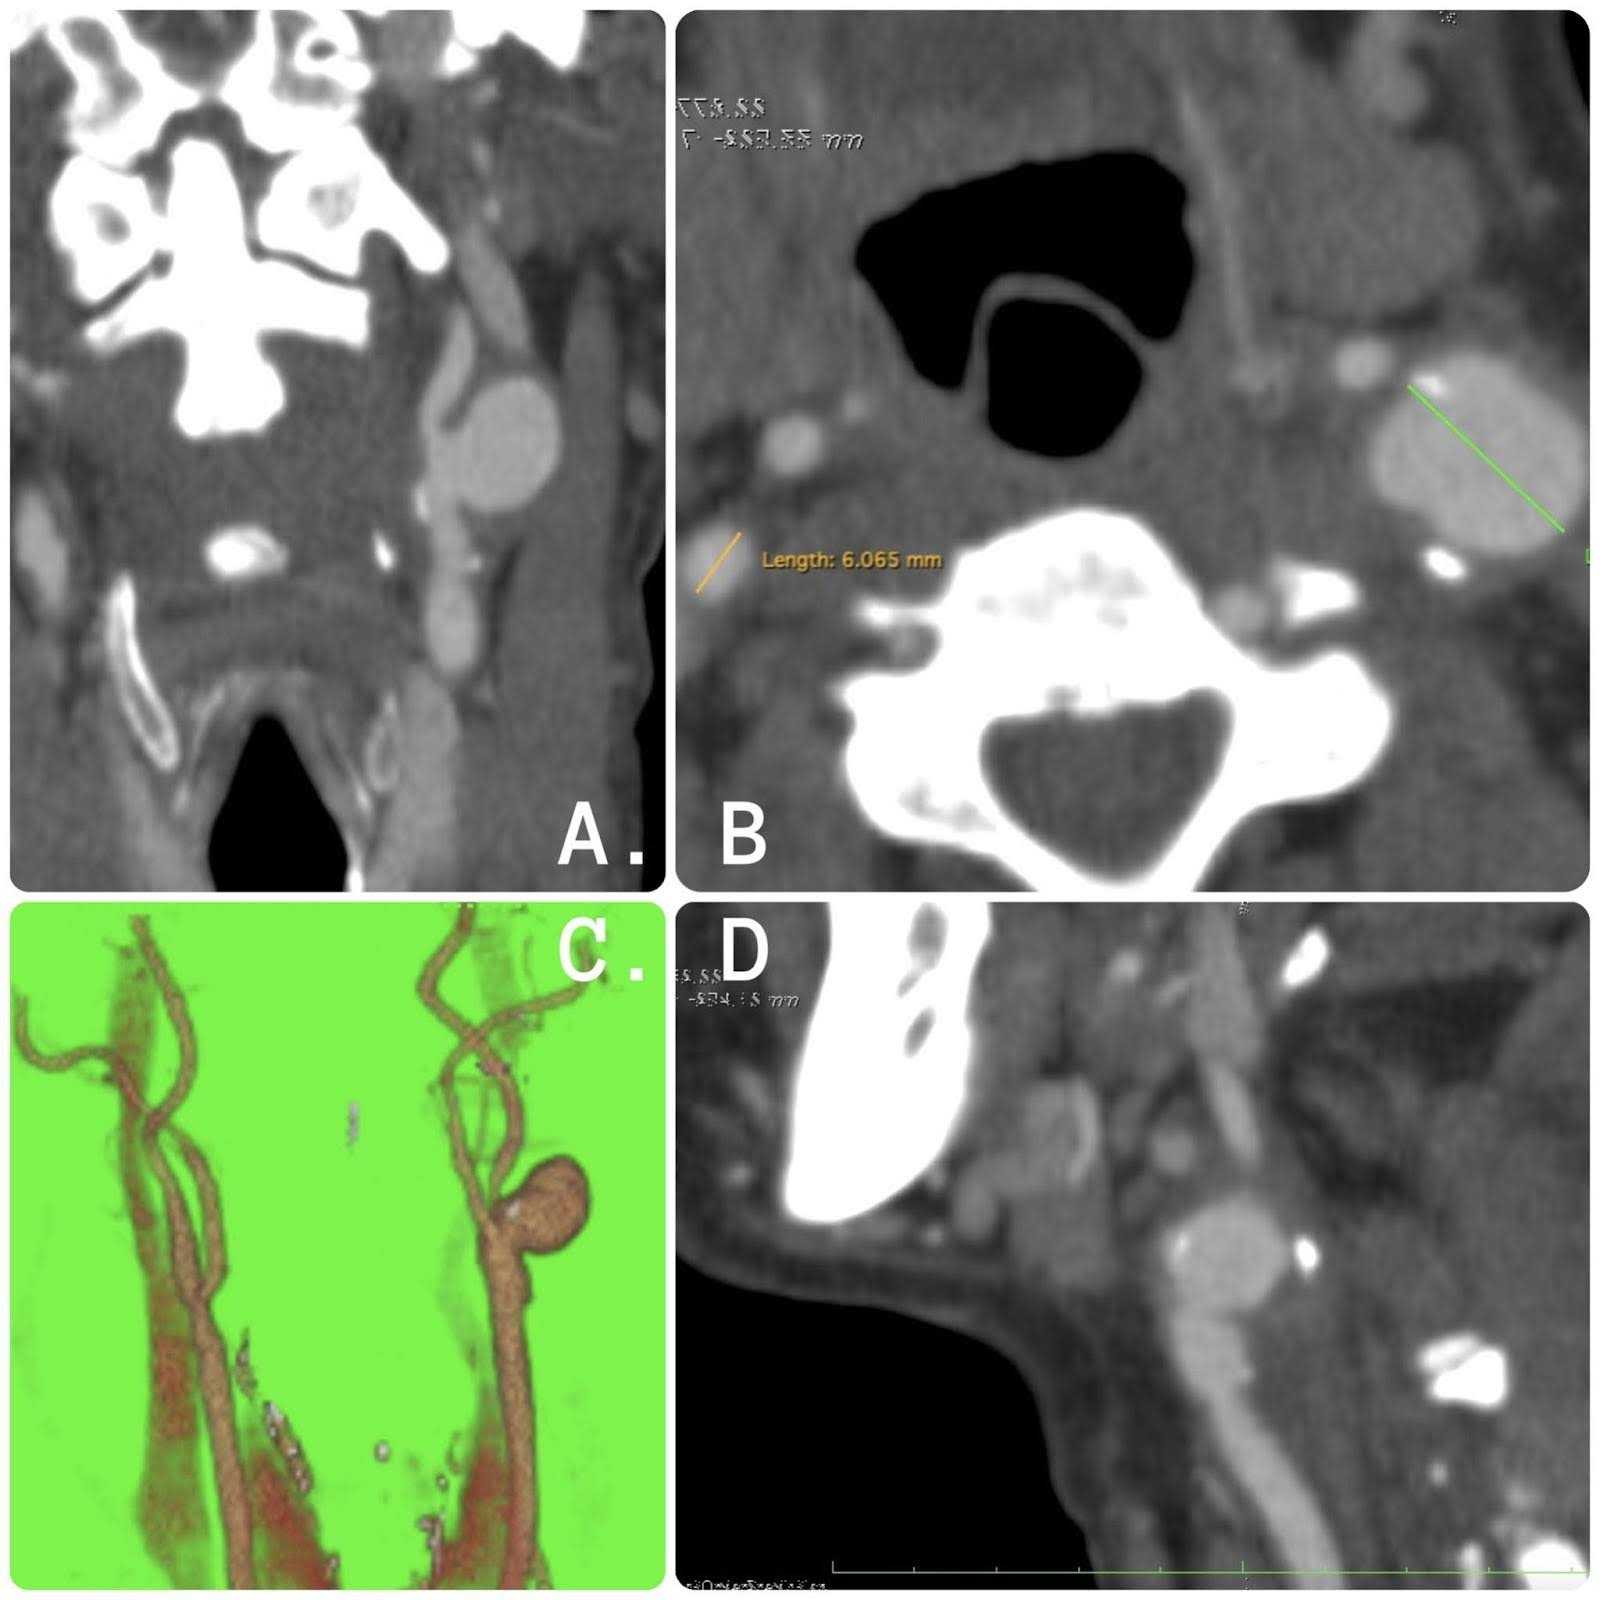

The patient's angiotomography presents the following finding: left internal carotid artery with a saccular-type aneurysm measuring 1.8 cm in its largest diameter as well as limited to the proximal portion of the bifurcation before the surgery. Patient tomography imaging can be seen in Figure 1.

Figure 1. Tomography images. (A) Coronal section with evidence of left internal carotid artery aneurysm with saccular morphology. (B) Axial section with evidence of left internal carotid artery aneurysm of 1.8 cm in greatest diameter. (C) Three-dimensional reconstruction. (D) Sagittal section with evidence of left internal carotid artery aneurysm with atherosclerotic plaque.